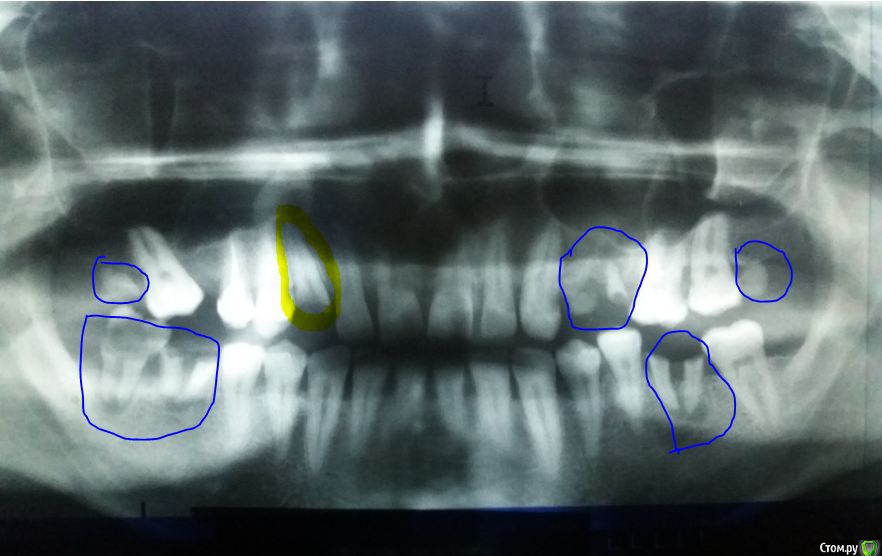

St. Опубликовано 1 апреля, 2020 Поделиться Опубликовано 1 апреля, 2020 Как минимум по снимку что обведено синим - удалять, желтым(верхний правый клык) лечить корневые каналы.При очном осмотре возможно еще что-то дополнительно.Перед плановой операцией удаление и санация очень желательны. Ссылка на комментарий

krokomot Опубликовано 1 апреля, 2020 Поделиться Опубликовано 1 апреля, 2020 нужно удалить как минимум 9 зубов. Ссылка на комментарий